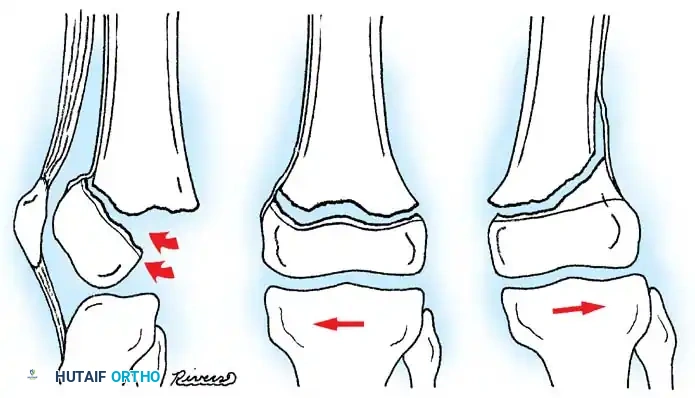

DISTAL FEMORAL PHYSEAL AND SUPRACONDYLAR FRACTURES

Fractures involving the distal femoral physis (Salter-Harris types) or the supracondylar region require distinct management. The distal femoral physis contributes 70% of the growth of the femur and 40% of the overall growth of the lower extremity. Consequently, anatomic reduction is paramount to minimize the risk of premature physeal closure and subsequent limb-length discrepancy or angular deformity.

AP radiograph demonstrating a displaced Salter-Harris II fracture of the distal femur.

Intraoperative fluoroscopy showing smooth Kirschner wire fixation crossing the physis to stabilize a Salter-Harris fracture.

Cannulated screw fixation of a distal femoral epiphyseal/metaphyseal injury, ensuring the threads do not cross the open physis.